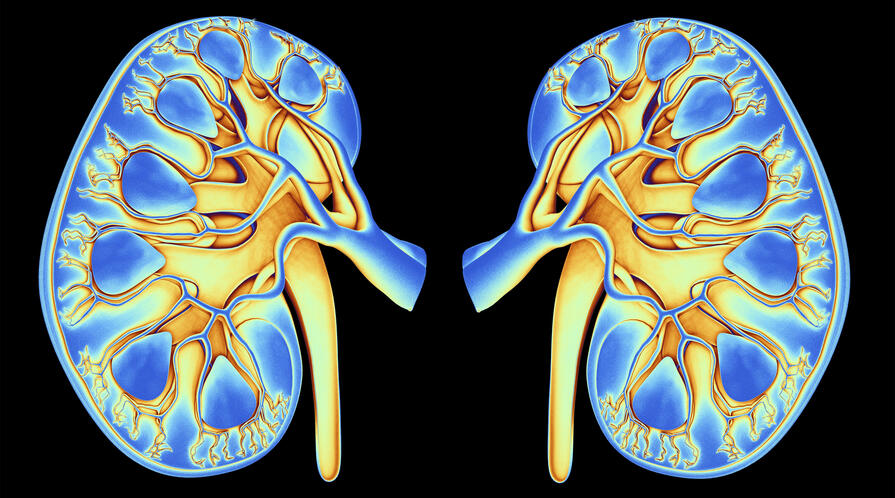

More than one in seven adults in the United States are believed to have chronic kidney disease, with the burden disproportionately impacting Black and Hispanic adults. A new Stanford study suggests a population-wide CKD screening could reduce these disparities.

Screening for chronic kidney disease at younger ages could prolong life expectancy and reduce health disparities among racial and ethnic groups—particularly for non-Hispanic Black adults, who are disproportionally affected by CKD, according to a new Stanford study.

More than one in seven adults in the United States, or about 35.5 million people, are believed to have chronic kidney disease (CKD), though many don’t know it. The burden of CKD disproportionately impacts racial and ethnic minority groups; the lifetime risk of kidney failure requiring dialysis or a kidney transplant is more than three times higher for non-Hispanic Black adults and 1.5-fold higher for Hispanics compared to non-Hispanic white adults.